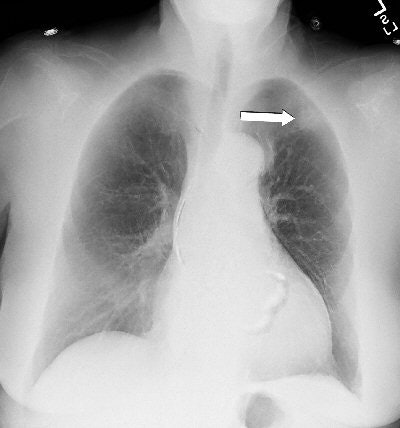

| Above: PA chest radiograph of an 86-year-old female. Below: Dual-energy subtraction image of figure above. The subtle left upper lobe mass is demonstrated (arrow). |